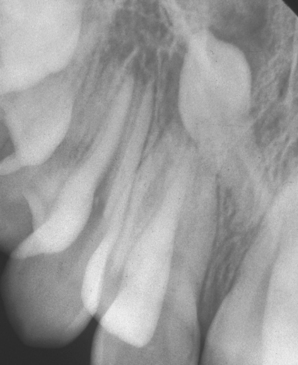

3. In Fig. 12.18 the upper right canine tooth has been surgically exposed.

(a) Describe the type of flap that has been used.

(b) Why has the excess tissue not been surgically excised at the same time?

(c) What other technique can be used to prevent the defect healing?

(d) What else could be done at the time of surgery to encourage eruption of the tooth?

image

Fig. 12.18 See question 3.